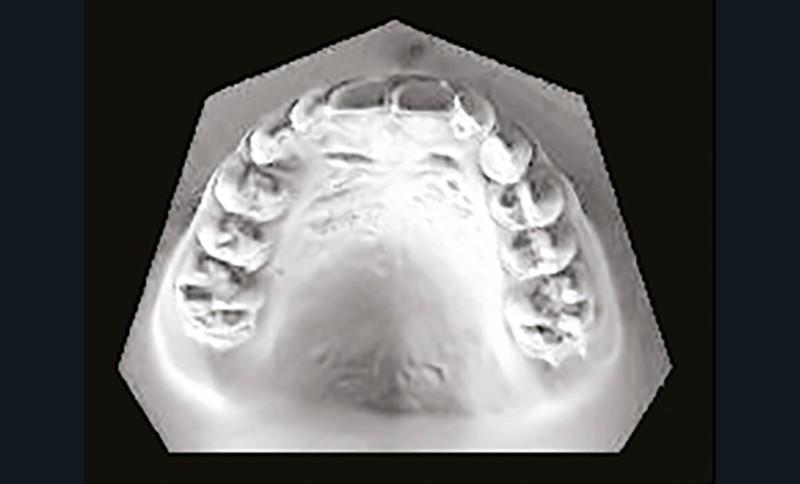

Son profil convexe s’inscrit dans un contexte de classe II squelettique par rétrognathie mandibulaire normodivergente sur un schéma de Classe II/2 avec supraclusion et encombrement modéré (fig. 1 à 7).

La formule dentaire est complète, avec un léger retard d’évolution des deuxièmes molaires (fig. 8).